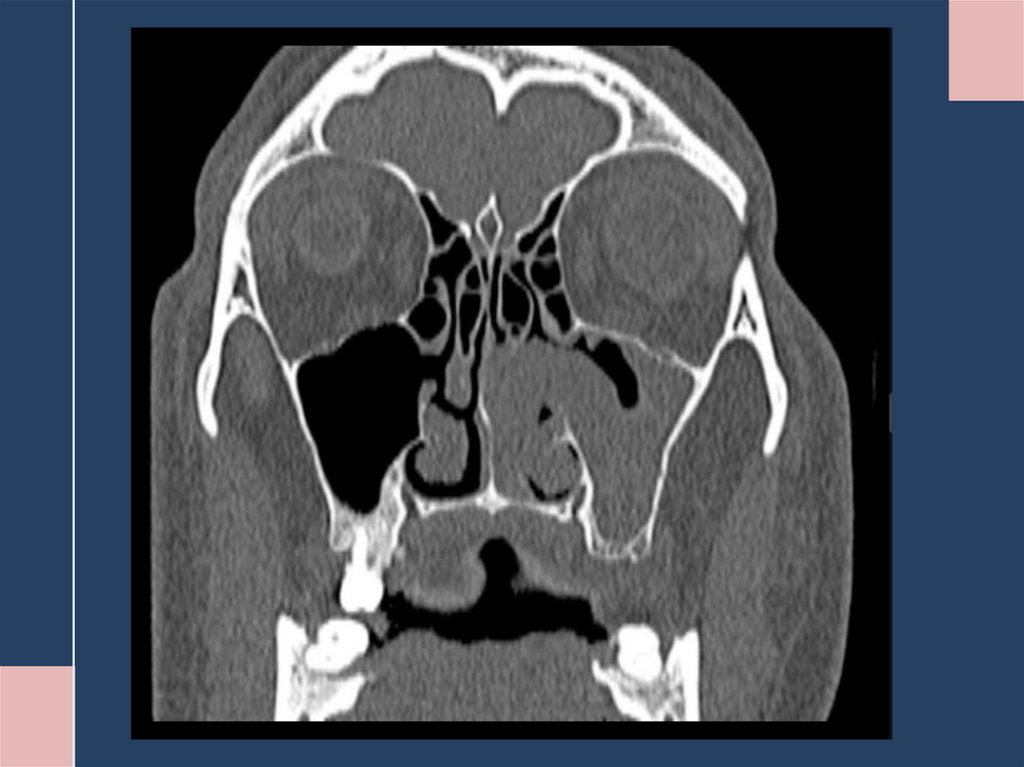

2. Лучевая диагностика:

Компьютерная томография (КТ) — метод выбора.

– Позволяет оценить костную деструкцию.

– Определяет точную локализацию и распространенность процесса.

– Характерные признаки: одностороннее затемнение пазухи, гомогенное образование

мягкотканной плотности, иногда с очагами обызвествления. Важный признак — симптом

"контралатерального отклонения" перегородки носа.